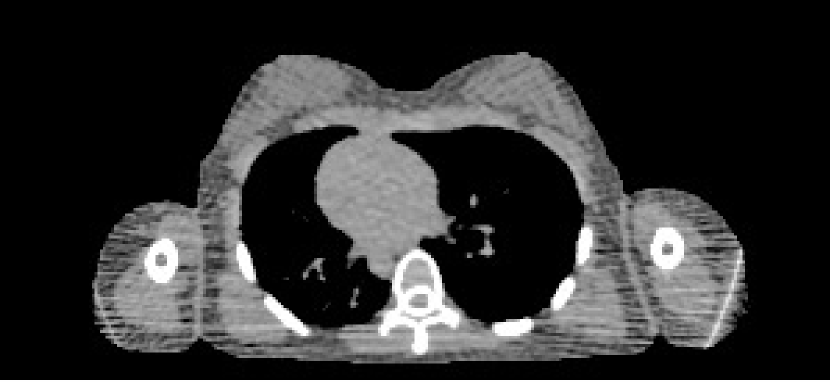

The data we used for our numerical reconstruction test were derived from the Adult Reference Computational Phantom (ICRP Publication 110,, 2009), which is a segmented image of defined density and chemical composition to represent real tissues. To investigate the ability to image metal implants, we inserted a pair of prosthetic hip joints (marked in green) with a solid titanium pin and shell. The slices through the chest and pelvis—which are the images we selected for testing—are shown in Figure 8. The resolution is 299×137299137299\times 137.

Refer to caption

(a) Chest test image

(b) Pelvis test image

Figure 8: Experimental data used: (a) is the oracle chest electron density; and (b) is the oracle pelvis electron density; both have a with display window of [0.8,1.2]